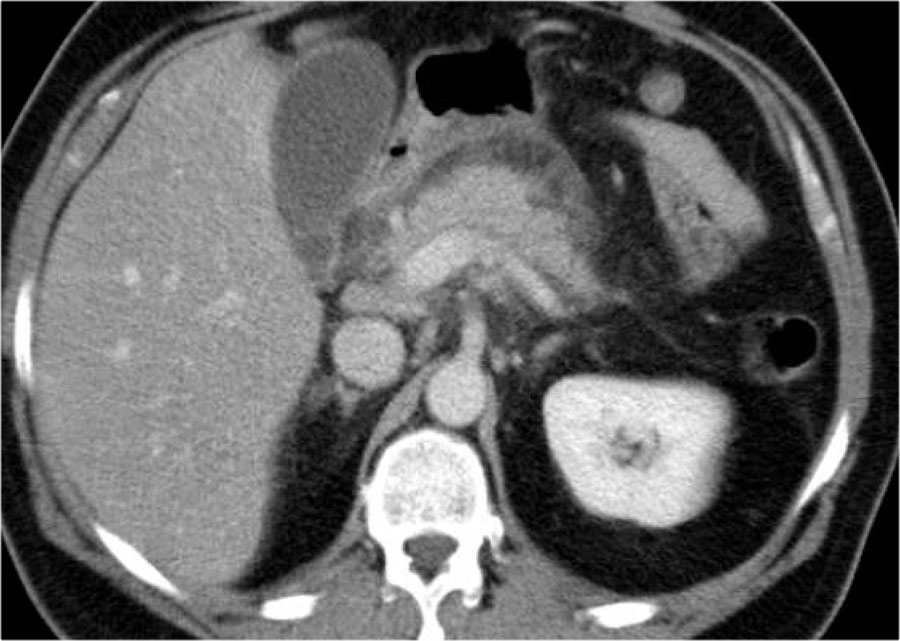

Các dấu hiệu bao gồm:

- Tụy ngấm thuốc bình thường toàn bộ.

- Các ổ dịch quanh tụy lan rộng, có tỷ trọng dạng lỏng và không lỏng trên CT.

- Có ít nhất hai ổ dịch, nhưng không có hoại tử nhu mô tụy (CTSI: 4).

- Vào ngày thứ 18, các ổ dịch quanh tụy mở rộng và xuất hiện thành không hoàn toàn.

Vào ngày thứ 5, ổ dịch này có thể được chẩn đoán là ổ hoại tử cấp tính có khả năng cao.

Vào ngày thứ 18, thành chưa hoàn toàn, nhưng có thể dự đoán rằng trong vài ngày tới đây sẽ trở thành ổ hoại tử được bao bọc với thành hoàn chỉnh.